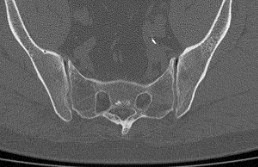

- сужение суставной щели (в норме она составляет 4-5 мм);

- на начальных стадиях заболевания возможно расширение суставной щели;

- на поздних стадиях патологии суставная щель полностью исчезает (полный анкилоз) или на КТ определяются «мостики» из соединительной ткани между суставными поверхностями (частичный анкилоз);

- уплотнение субхондральной (подхрящевой) кости, которое обычно сильнее выражено со стороны подвздошной кости, чем крестца;

- появление кист в субхондральной кости;

- эрозии на суставных поверхностях.